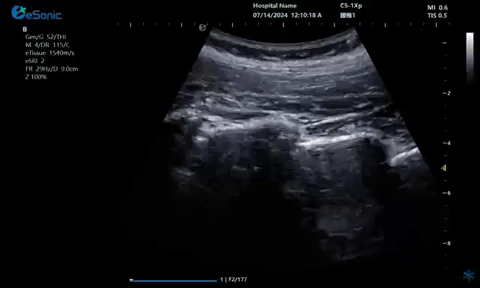

超声引导下神经根阻滞,也可以

做腰神经后支